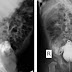

| Reprodução/Radiology Case Reports |

A equipe realizou exames por mais de um ano após o nascimento da criança para entender como funciona o sistema urinário único do paciente. Em exames de imagem com um corante específico, foi identificado que o bebê tem uma fístula, ou seja, uma ligação anormal entre a bexiga e o reto – que fica no final do intestino.